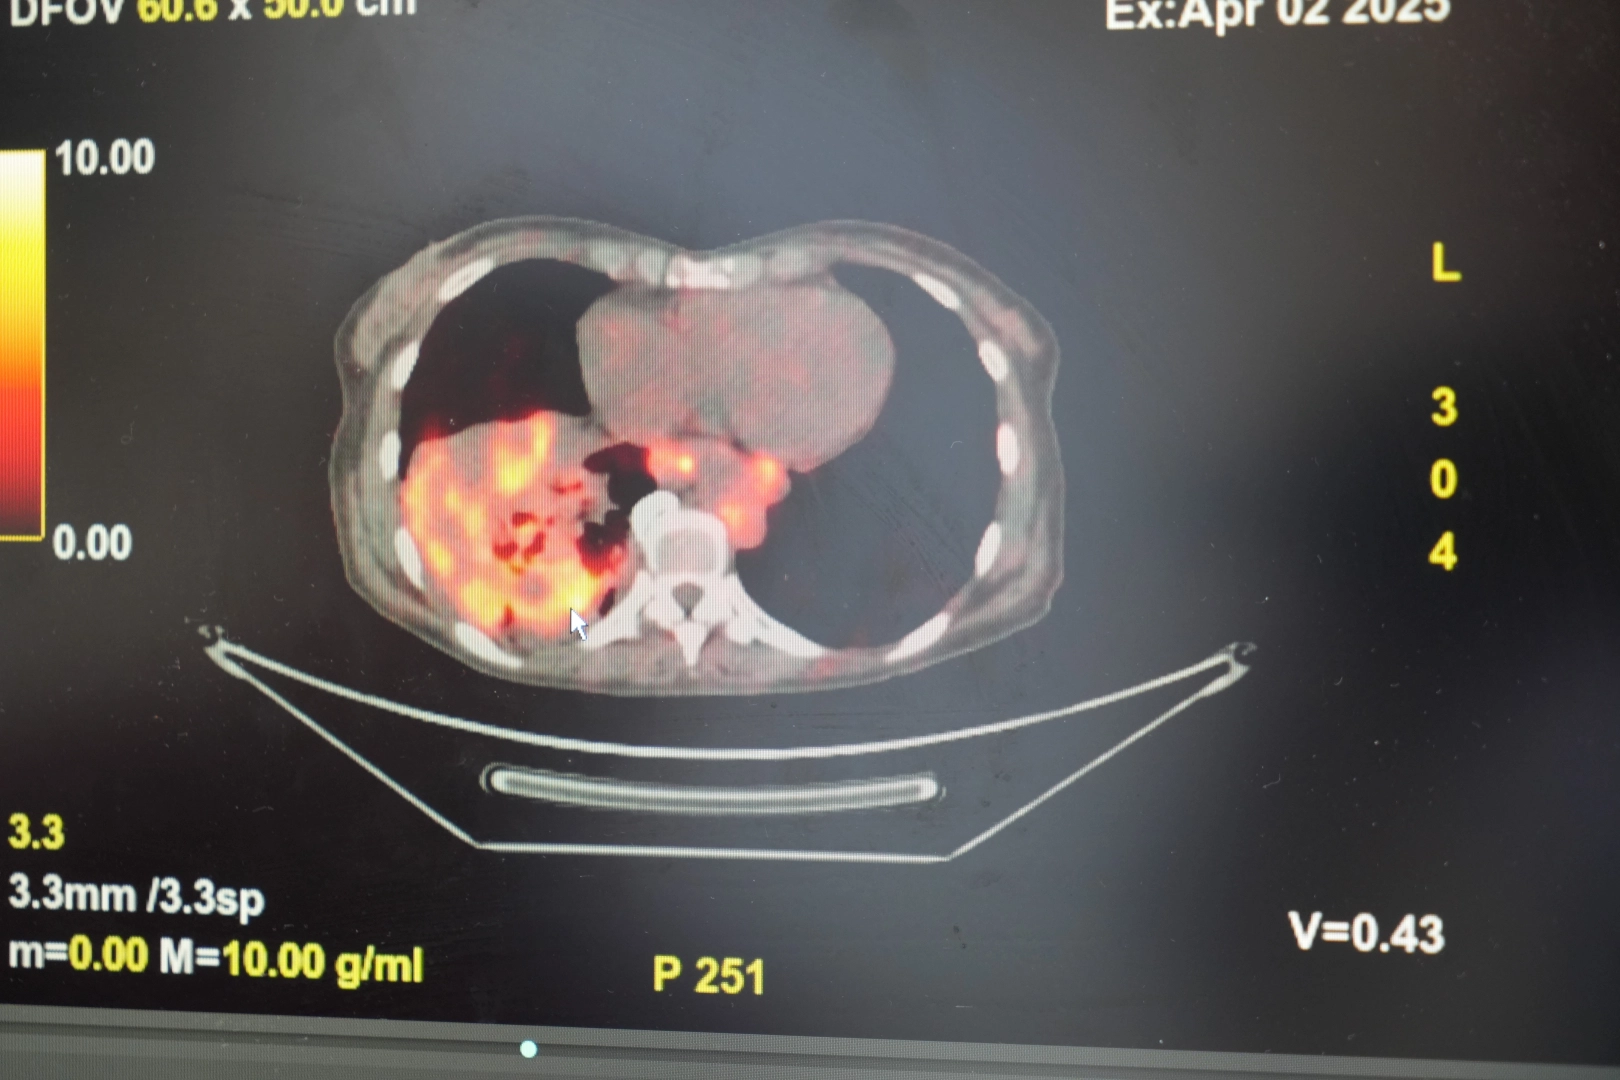

Göğüs Hastalıkları Uzmanı Prof. Dr. Şevket Özkaya, son yıllarda sigara kullanmayan bireylerde de akciğer kanseri vakalarının dikkat çeken bir oranda arttığını belirterek, özellikle kadınlarda görülen adenokarsinom tipi akciğer kanserinin artış gösterdiğine dikkat çekti. Bu konuda yapılan son araştırmalara değinen Özkaya, akciğer kanseri teşhislerinin yaklaşık yüzde 20’sinin hiç sigara içmemiş bireylerde konduğunu söyledi. "Kadınların anatomisi ve bağışıklık sistemi risk faktörlerini artırıyor" Prof. Dr. Şevket Özkaya, konuyla ilgili yaptığı değerlendirmede, "Hiç sigara içmemiş kadınların akciğer kanserine yakalanma ihtimali, sigara içmemiş erkeklere kıyasla iki kattan fazladır. Kadınlarda daha sık görülen otoimmün hastalıklar ve bağışıklık sisteminin fazla çalışmasına bağlı kronik iltihaplanmalar (inflamasyon) bu riski artırabiliyor. Ayrıca bağışıklık sistemini güçlendirmek için kullanılan bazı ilaçlar, vücuttaki değişimlere karşı aşırı yanıt oluşmasına neden olarak kanser gelişimine zemin hazırlayabiliyor" dedi. "Kadınlar hava kirliliğine karşı daha savunmasız" Özkaya, kadınların akciğer yapısının da bu duruma katkı sunduğunu belirterek, "Kadınların akciğerleri erkeklere göre daha küçük ve daha dar hava yollarına sahip. Bu da ince partiküllerin (PM2.5 gibi) daha derinlere inerek akciğerde birikmesine neden olabiliyor. Hava kirliliği, ev kimyasalları, iş yerinde maruz kalınan zararlı maddeler, hatta ev içi yemek pişirme dumanları bile riski artırabiliyor" diye konuştu. "Ev içi maruziyetlere dikkat edilmeli" Prof. Dr. Özkaya, sigara içmeyenlerde artan akciğer kanseri riskinin ardında çok sayıda çevresel faktör olduğunu vurguladı: "Radon gazı, pasif içicilik, odun ya da kömürle ısınan yetersiz havalandırılmış ortamlar, yemek pişirme sırasında oluşan duman gibi unsurlar özellikle ev hanımı olan kadınları tehdit ediyor. Kadınların daha fazla zaman geçirdiği iç mekânlar, hava kirliliğine maruz kalma açısından ciddi bir risk alanı. Bu nedenle, bu gruplar için önleyici stratejiler geliştirmek hayati önem taşıyor" şeklinde konuştu. "Radyasyona maruziyet riski evlerde başlıyor" Dünyanın en prestijli tıp dergilerinden yayımlanan bir araştırma üzerinde açıklama yapan Prof. Dr. Şevket Özkaya, araştırmaya göre, sigara içmeyenlerde en sık görülen tür olan akciğer adenokarsinomu, kadınlarda akciğer kanserlerinin yaklaşık yüzde 60’ını oluşturduğunu söyledi. Prof. Dr. Özkaya, sigara dışındaki risk faktörlerinin başında radon gazının geldiğine dikkat çekerek, "Radon gazı, evlerimizde farkında olmadan soluduğumuz, renksiz, kokusuz, tatsız ve radyoaktif bir gazdır. Müsaade edilen değerlerin üzerinde solunduğunda akciğer kanseri riskini artırıyor. Radon gazı özellikle taş, toprak ve çimento gibi yapı malzemelerinde doğal olarak bulunuyor. Bu maddelerden ortama sürekli yayılan gaz, solunum yoluyla akciğerlere ulaşıyor" ifadelerini kullandı. Evlerin yapıldığı arazilerde bulunan doğal uranyumun radona dönüşmesiyle bu gazın evlerin zemin katlarından iç ortama sızabildiğini vurgulayan Özkaya, bu durumun bölgeden bölgeye ve ülkeden ülkeye farklılık gösterdiğini kaydetti. Özellikle soğuk ve rüzgarlı havalarda, evin iç basıncının düşük, dış basıncın yüksek olması nedeniyle radon gazının iç ortamdaki oranının arttığını ifade etti. Ev hanımları risk altında Özkaya şunları söyledi: "Son yıllarda özellikle ev hanımı olan kadın hastalarda ve sigara içmeyenlerde akciğer kanseri vakalarını daha sık görmeye başladık. Ev ortamında uzun süre bulunan bireylerde radon gazına maruziyet artabiliyor. Bu nedenle ev içi hava kalitesi ve radon gazı düzeylerinin ölçülmesi büyük önem taşıyor. Hekimler olarak bu konuda toplumsal farkındalık oluşturulması gerektiğine inanıyoruz." Özkaya ayrıca, asbest, kimyasal ajanlar, güneş ışınları, radon gazı ve HPV enfeksiyonlarının da kanser yaşını erkene çektiğine vurgu yaparak, bu tür çevresel faktörlere karşı önleyici tedbirlerin önemine dikkat çekti.